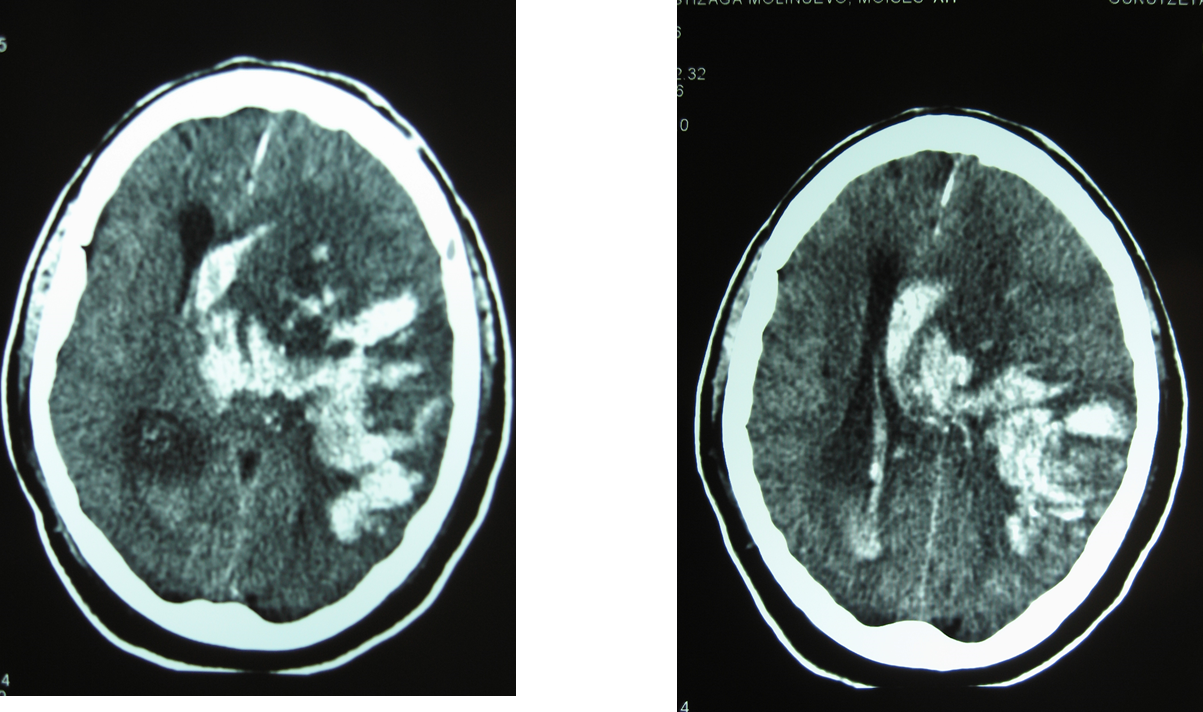

Y la TAC cerebral a las 24 horas:

En este caso se trata de una hemorragia en el lugar de la isquemia cerebral en el territorio de la arteria cerebral media izquierda y en el contralateral: